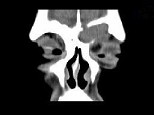

- 单项选择题男,53岁, 左眼痛、突出3年,结合图像, 最可能的诊断是 ( )

A、淋巴瘤

B、骨膜下脓肿

C、黏液囊肿

D、眼型Graves病

E、良性混合瘤